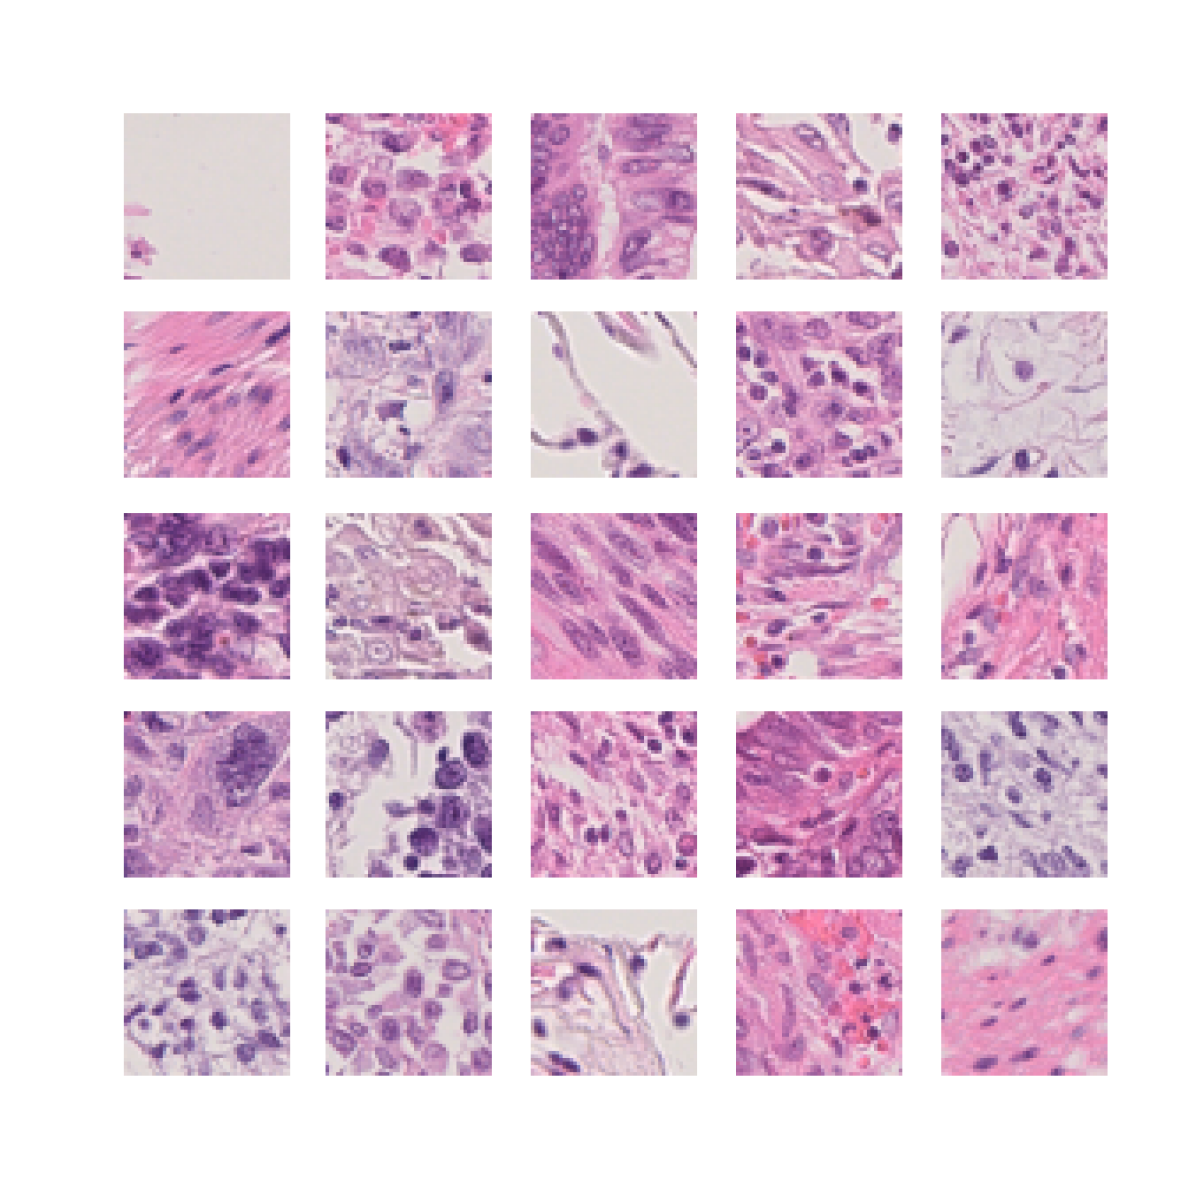

We also analyse the activation maps for each model using GradCAM as described in section S3. This offers more insight into the areas of the image which are contributing most heavily to the models’ representations. In Figure 4(b) we present some representative examples, however, a larger selection which was chosen at random is presented in Figures S10 to S25. The larger selection makes it easier to see the emergent patterns, including that privileged Siamese models tend to mainly identify features which are strongly present in both inputs, while unprivileged Siamese models tend to learn more diffuse features that are not specific to one cell phenotype or image region. TriDeNT ♆ incorporates both sets of features, learning both features specific to the privileged data and more the general features associated with unprivileged Siamese networks.

We can see in Figure 4(b) panel A that for ERG, the privileged Siamese model focuses almost exclusively on any nuclei which could be endothelial cells. As there are very few endothelial cells in the dataset, it could be an effective strategy to identify anything that could potentially be an endothelial cell to minimise the difference between the representations of the H&E model and the IF mask model. In the corresponding unprivileged Siamese image, we see that the model identifies some of these nuclei, albeit less strongly, but also focuses heavily on the other tissue and even the background, while strongly fixating on two spots of debris in the center of the image. This model has less ‘incentive’ to learn the weak features related to endothelial cells as these occur rarely and are not easy to detect, while more generic strong features such as the presence of connective tissue and the prevalence of background are more common and predictable from augmented images. We see that TriDeNT ♆ combines these two feature sets, strongly identifying nuclei while also identifying the connective tissue.

In panel C we see a similar pattern, with the privileged Siamese model fixating solely on the nuclei, while the TriDeNT ♆ model takes a more balanced approach. The unprivileged Siamese model appears to focus on a single cluster of nuclei while neglecting others, and similarly identifies an area of fibroblasts with its distinctive pattern but does not others.

In contrast to panels A and C which represent models with poor privileged Siamese results, panels B and D represent models whose privileged Siamese results were comparable to both TriDeNT ♆ and even the supervised baseline. It is therefore interesting to note that there are far more similarities between the privileged Siamese and TriDeNT ♆ models in both cases. Particularly in panel B, TriDeNT ♆ and the privileged Siamese model return virtually identical heatmaps, with both strongly identifying epithelial nuclei and neglecting the same areas of connective tissue. The unprivileged model in this case appears to focus solely on the centre of the image, giving a significantly different heatmap to the other panels.

Panel D again shows the previous pattern, with the privileged Siamese model identifying the features strongly present in the privileged data – fibroblasts – while neglecting the nuclei present. TriDeNT ♆ also strongly identifies the connective tissue, but, unlike the privileged Siamese model, does not completely neglect the nuclei. The unprivileged Siamese model primarily identifies background, and does not appear to identify the nuclei in this example.